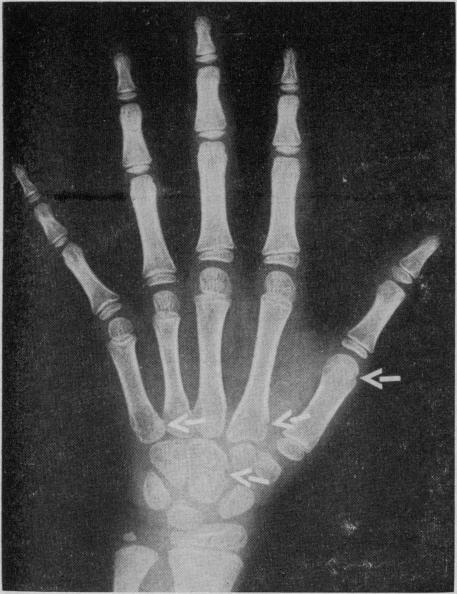

Reid H E

Can Med Assoc J. 1968 Mar 23;98(12):584-9.